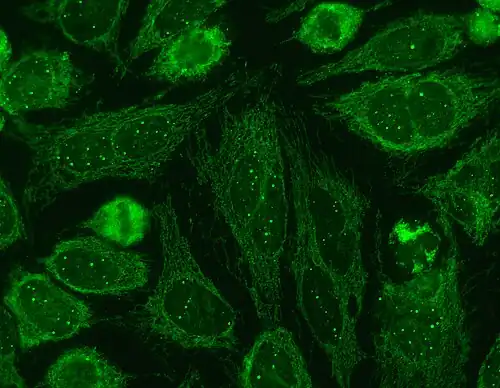

Immunofluorescence staining pattern of sp100 antibodies (nuclear dots) and antimitochondrial antibodies